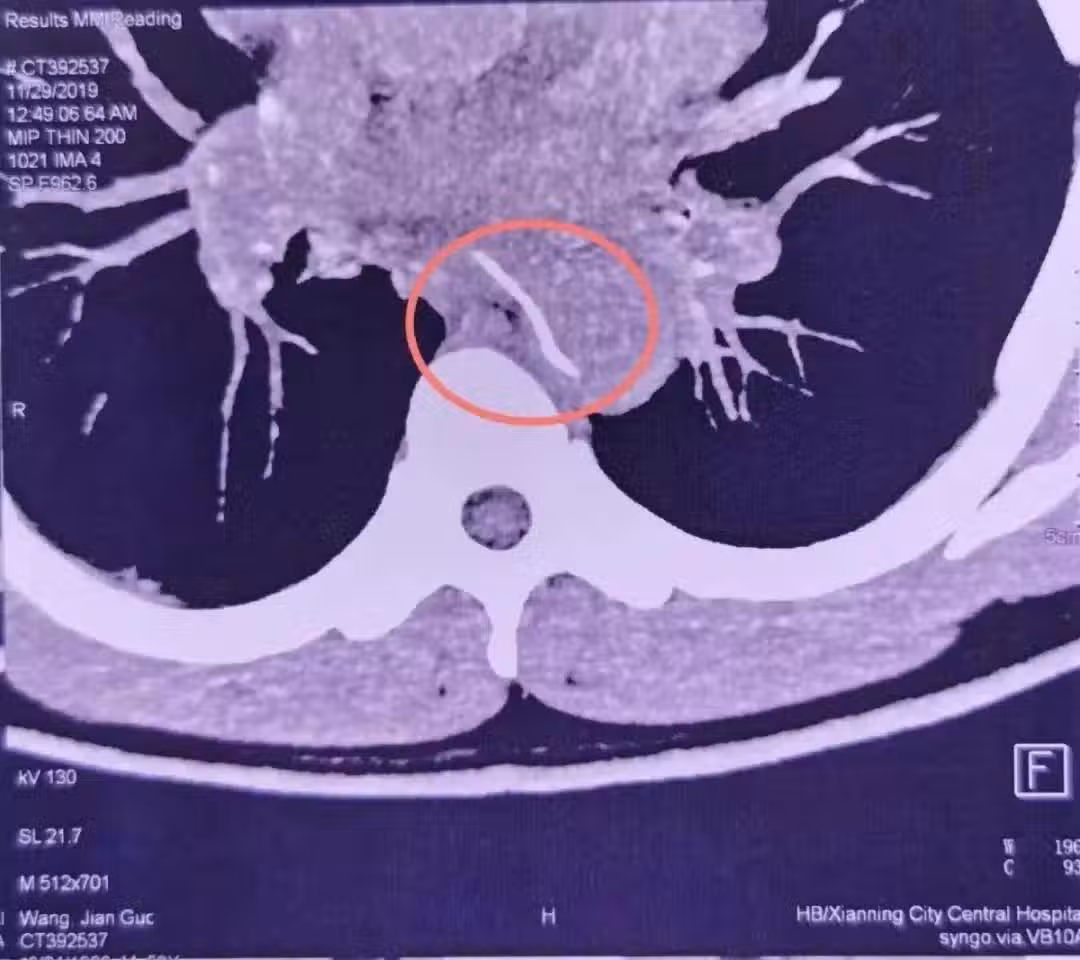

胸主動脈,作為人體最粗大的動脈血管,血管壓力很高,如果形成破口,出血就會呈噴射狀。這個場景就好比「大壩決堤」,幾乎沒有搶救的機會。

就算醫生再見多識廣,也會覺得這很罕見,甚至一開始以為裡面的是塑料牙籤。畢竟這麼長、這麼尖的魚刺,人怎麼能吞得下去呢?

因為大量出血,此時男子臉色蒼白,還出現了失血性休克。情況緊急,什麼核酸檢測,什麼陰性結果顯然都是等不及的。